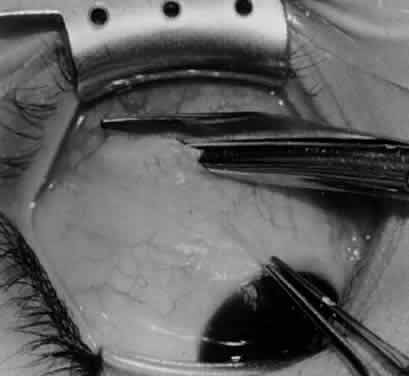

Fig. 1. The standard inferior-temporal fornix incision is made through the conjunctiva and Tenon's capsule with a Westcott scissors. The incision is placed about 8 mm posterior to the limbus, anterior to the fat pad.

Fig. 2. After the lateral rectus muscle is hooked with a Stevens and then a Green muscle hook, the lateral rectus muscle is tented to allow placement of a 4-0 silk suture beneath the insertion of the lateral rectus muscle. The needle tip should glide along the inferior surface of the muscle hook to avoid laceration of the lateral rectus muscle or laceration or penetration of the globe.

Fig. 3. The eye is retracted superonasally with the 4-0 silk traction suture. The suture is attached to the drapes with a hemostat. A Stevens hook is placed along the inferior border of the lateral rectus muscle and drawn temporally. A von Graefe hook is placed within the incision and drawn inferotemporally to expose the inferior oblique muscle.

Fig. 4. A stiff iris repositor can be placed against the sclera to depress the sclera and enhance the view of the inferior oblique muscle. The inferior temporal vortex vein adjacent to the Stevens hook is retracting tissue along the inferior border of the lateral rectus muscle. The second Stevens hook is pointing to the inferior oblique muscle.